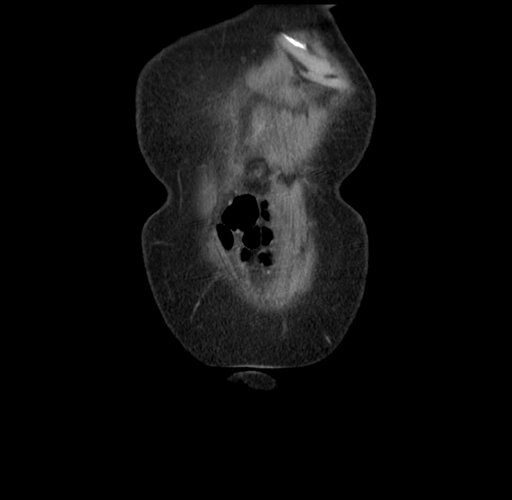

MRI T1